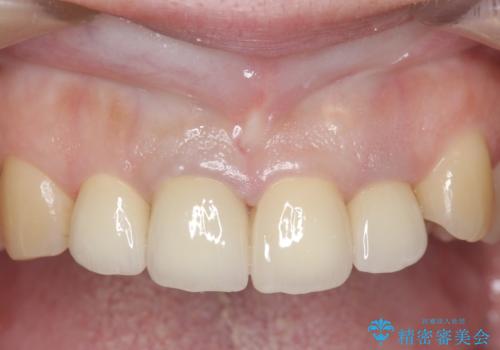

- 前歯の色や長さ、歯茎との隙間の金属が気になるのでセラミックで治療したいといらっしゃった方の症例です。

見た目改善のため、前歯4本をオールセラミッククラウン(スペシャル)で補綴しました。

前歯の補綴ではオールセラミッククラウンを希望される患者様が多いですが、オールセラミッククラウンの中でも、エコノミー、スタンダード、スペシャル、エクセレントとランクがあります。

その中でも特に審美性が高いのがスペシャル、エクセレントです。スペシャル、エクセレントは口腔内写真をもとに熟練の技工士が、患者様の口腔内に合わせたオーダーメイドのクラウンを製作致します。